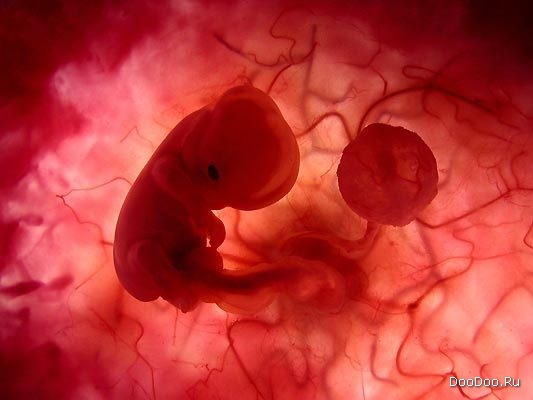

Восемь недель. Этот зародыш в состоянии пинаться и двигать ручками вверх и вниз.

Зародыш мягко перемещается в матке.